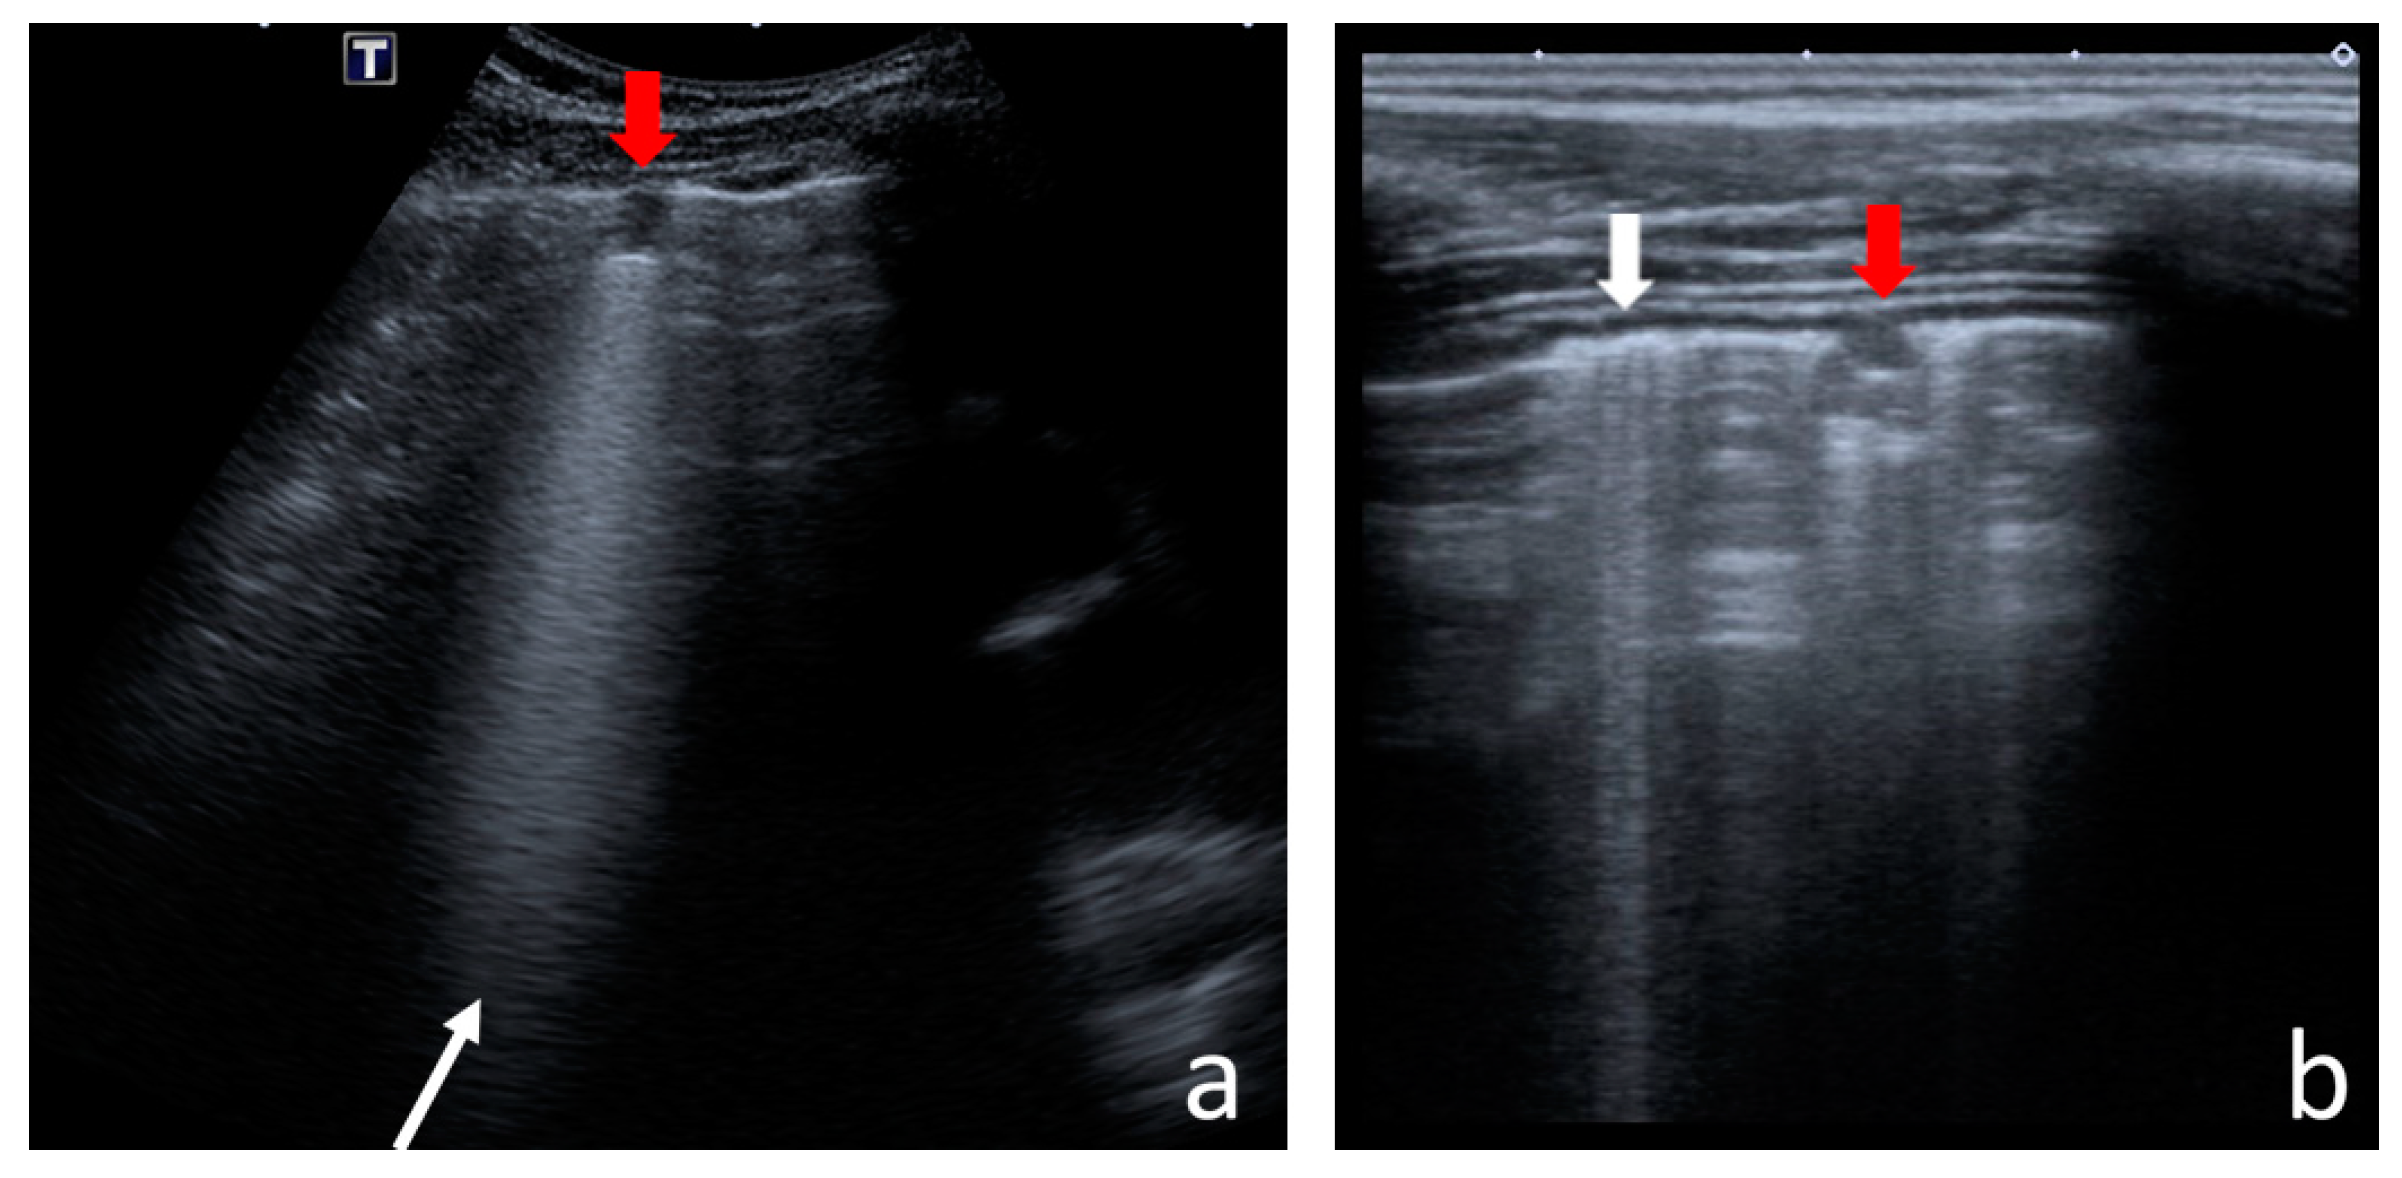

- Consolidations—hypoechoic, tissue-like areas: (a) small (≤10 mm) (Figure 6), and (b) major (>10 mm) (Figure 7); usually, major consolidations have the following associated features: the loss of pleural line echogenicity over the area of consolidation, absence of A-lines, presence of dynamic or static air bronchogram/air trapping and vascular pattern (in CD option) within the area, C-lines below the area, B-lines surrounding it [17,31];